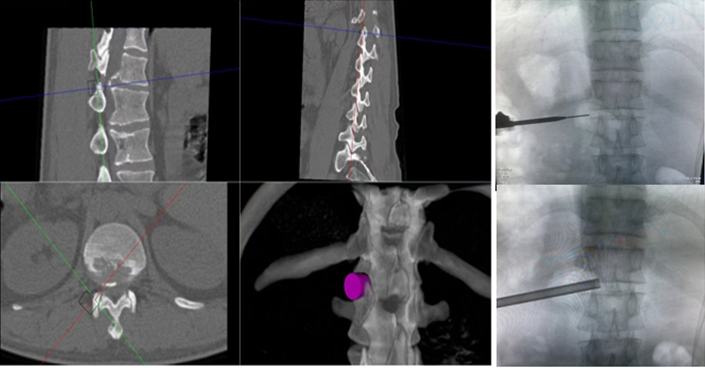

患者36岁,因肛周及会阴部胀痛麻木2年,加重1月入院。辗转多所医院,均建议采取传统外科开放手术治疗,患者因担心手术风险,迟迟不愿手术。经多方打听,患者慕名找到李全义主任医师,李全义主任医师接诊后,仔细研究患者的疾病特点,腰椎间盘突出症常见于低位椎间盘(L4/5、L5/S1),而该患者属于高位椎间盘突出(胸12/腰1节段),并且已经引起了马尾综合征,表现为会阴部及鞍区疼痛、麻木、二便障碍,高位椎间盘突出因高位椎管不如低位椎管容积大,在穿刺时容易损伤神经,造成严重并发症。与患者经过充分的沟通,决定采用目前骨科前沿技术-----机器人辅助微创手术。在病院主任刘时璋教授的带领下,李全义主任医师团队顺利为患者实施ORTHBOT脊柱机器人辅助椎间孔镜下胸12腰1髓核摘除、椎管扩大减压术,手术在局部麻醉下进行,以机器人辅助微创手术解除了患者的痛苦,减少手术创伤及并发症,缩短手术时间。

椎间孔镜在治疗脊柱相关疾病方面,尤其在治疗腰椎间盘突出症,具有创伤小、恢复快、花费少、床位周转快等优点,但椎间孔镜在术中穿刺过程中,需要反复调整穿刺针位置,需要较多的透视,特别是高位椎间盘突出症患者,稍有不慎便引起严重并发症。骨科手术机器人利用术前患者的影像学资料,模拟建立穿刺路径及各项参数,能极大地优化手术方案使其更加精准、更加安全、更加有效,显著降低了在穿刺过程中反复操作给患者造成损伤,极大程度上有效避免了严重并发症的发生。

ORTHBOT脊柱机器人术前设计及术中穿刺